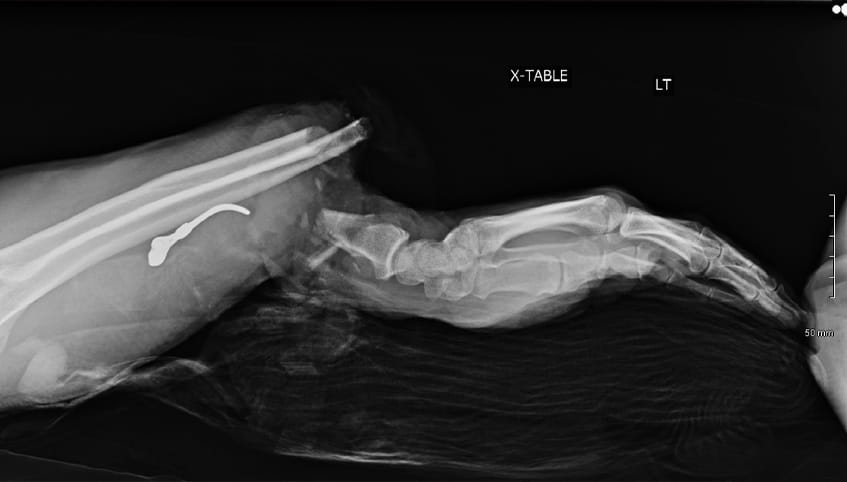

Nearly finished cutting some small pieces of wood, Steve stood, turned and snagged his shirt in the blade guard of an electric saw. The saw caught and almost completely severed Steve's left arm.

A surgical team performed an intricate 8-hour microsurgery to reattach Steve's forearm. Having completed fellowships in hand and upper extremity surgery, and addressing traumatic injuries such as this on a weekly basis, the team offered some of the region's best care in replantation and functional recovery.

Surgeons performed Steve's surgery under a microscope. They first plated and screwed the severed bones into place and then used sutures finer than a human hair to reconnect transected nerves, veins, blood vessels and tendons.